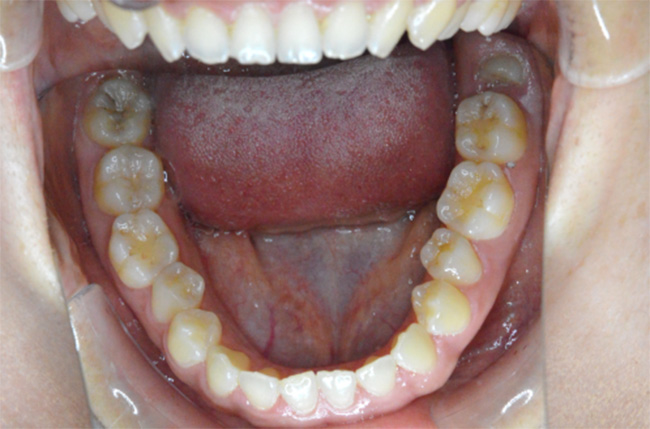

治療開始時